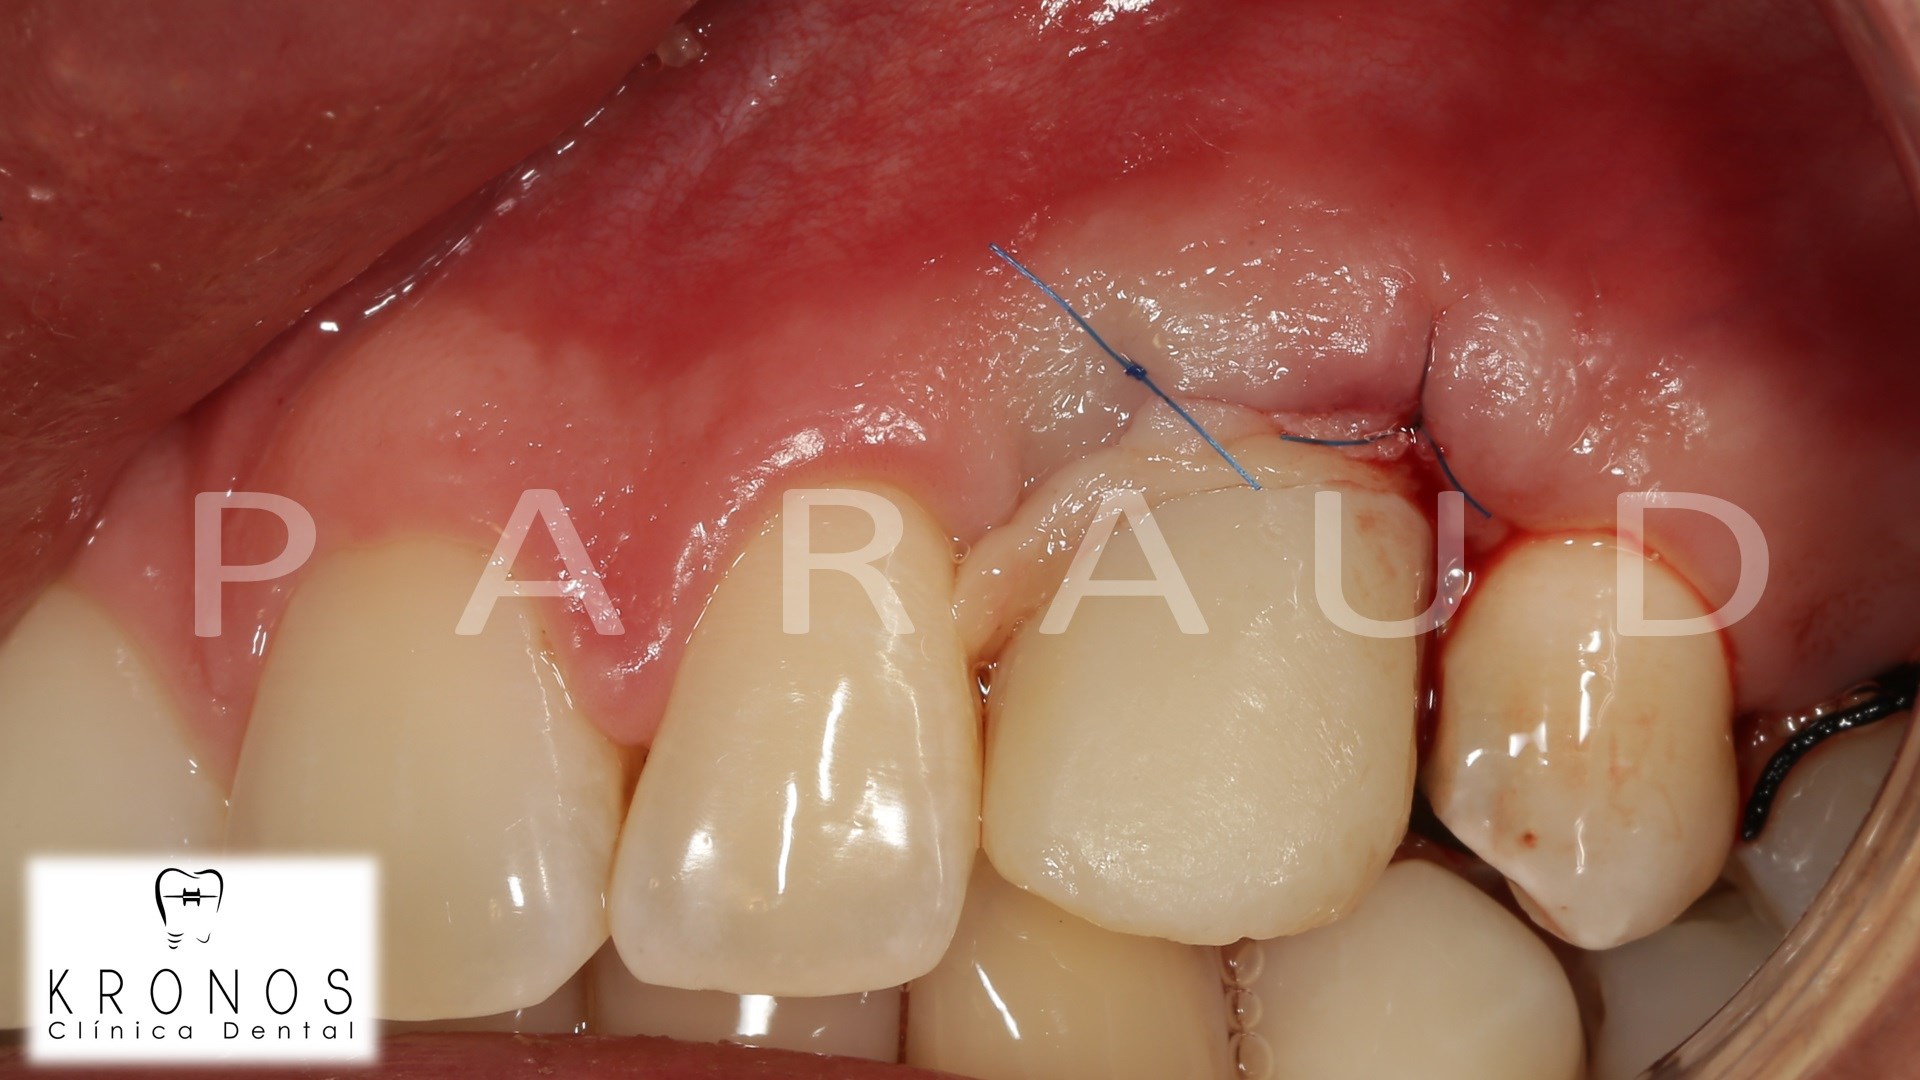

Clinical case: AnyRidge immediate loading

- Courtesy of Dr. Andres Paraud Freixas, Chile -

AnyRidge, ISQ value, initial stability, immediate loading, KnifeThread, maxillary anterior, Mega ISQ, Dr. Andres Paraud Freixas

AnyRidge implant system, Mega ISQ, Digital prosthesis

“Patient’s smile was recovered on the day of surgery

with reliable & highly-aesthetic results using AnyRidge & R2GATE. ”